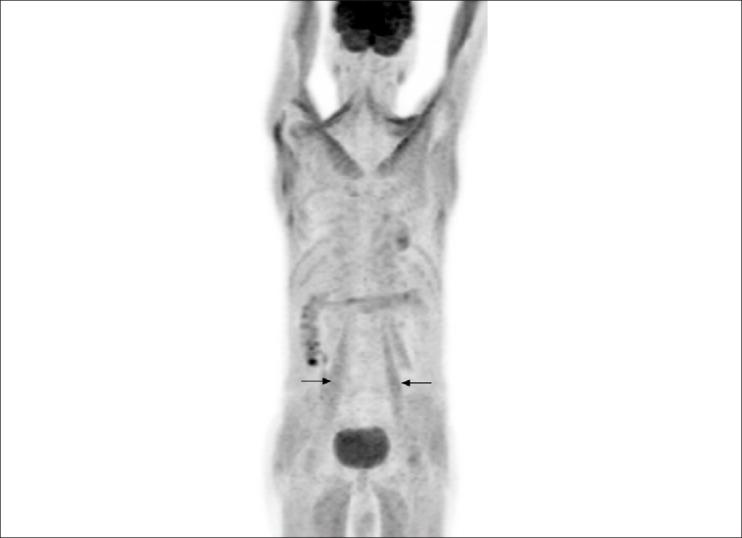

F-18 fluoro-deoxyglucose (FDG) uptake in the thyroid and thymus is well reported in patients with Graves' disease. Incidental skeletal muscle uptake has also been reported in other non-musculoskeletal (benign and malignant) pathologies. We report a patient of Graves' disease showing symmetrical skeletal muscle uptake but no thyroidal or thymus uptake of FDG.

https://cdn.ncbi.nlm.nih.gov/pmc/blobs/ba11/3543583/227da79570e4/IJNM-26-155-g001.jpg